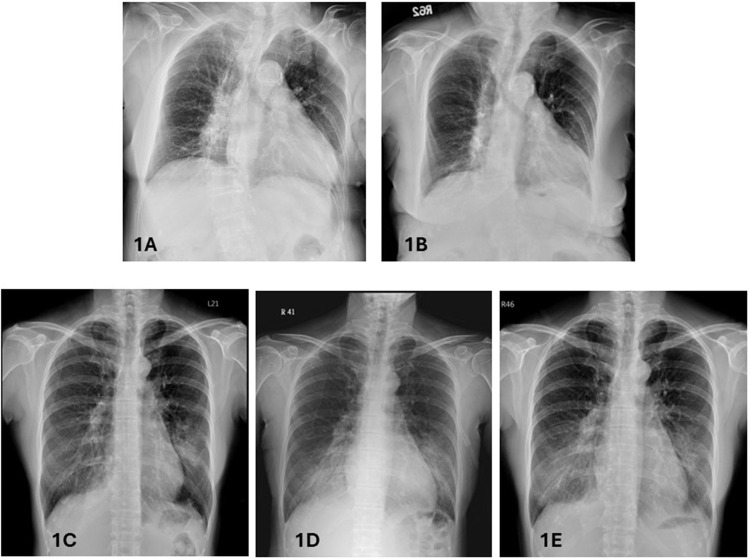

Results: Following Palivizumab administration, both patients exhibited clinical improvement, including resolution of fever and improvement in oxygenation and radiographic findings. Both patients were discharged in stable condition without the need for supplemental oxygen.